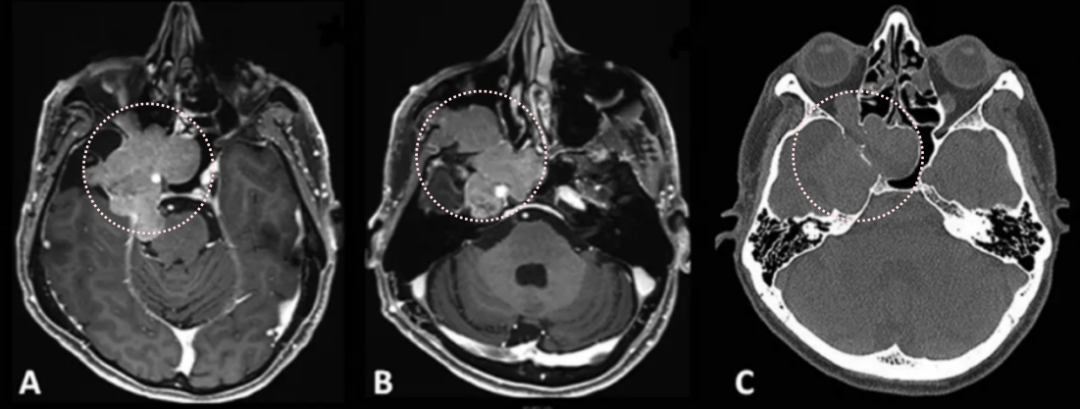

2012年,53岁的Leo突然发现自己嗅觉减退、视力下降时,就医检查发现右侧梅克尔腔脑膜瘤,随即进行了手术。谁能想到7年过后,脑膜瘤再次卷土重来,出现严重的V1(嗅神经)、V2(视神经)和V3(动眼神经)感觉减退和疼痛,症状比第一次手术前还要严重。磁共振成像(MRI)显示肿瘤大面积复发,延伸至海绵窦(CS)、后颅窝(PF)、蝶窦(SS)、翼腭窝(PPF)和颞下窝(ITF)。

患者术前影像。(A)术前轴位T1加权钆增强磁共振成像(MRI),显示脑膜瘤延伸至后颅窝、海绵窦、眼眶和蝶窦。(B)肿瘤延伸至中颅窝、翼腭窝和颞下窝。(C)术前轴位计算机断层扫描(CT)显示蝶骨大翼侵蚀和蝶窦受累。